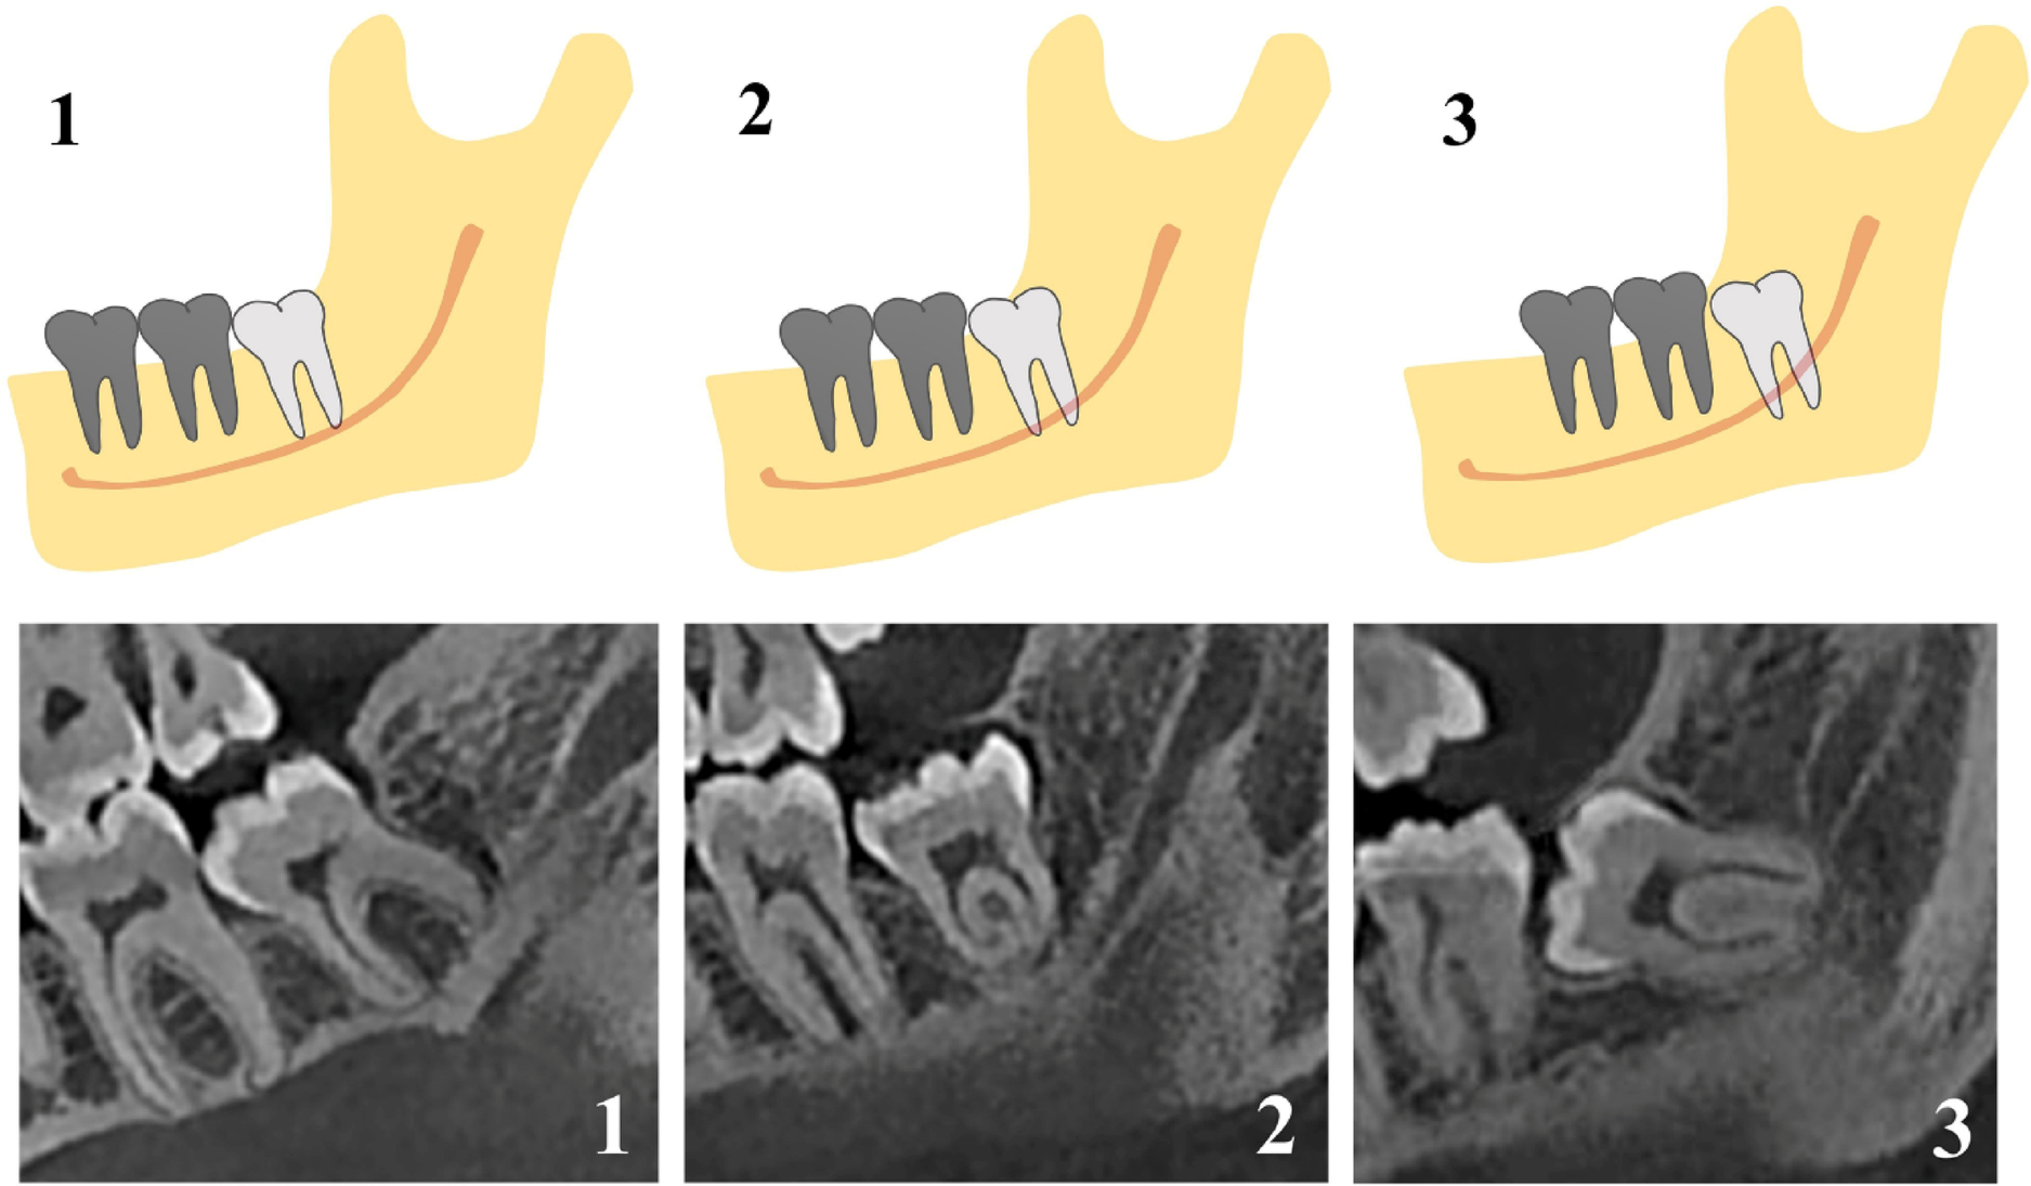

Evaluation of the relationship between the gonial angle and the pattern of the impacted mandibular third molar by cone beam computed tomography

This study evaluated the relationship between the gonial angle and the impaction patterns of mandibular third molars (M3Ms...